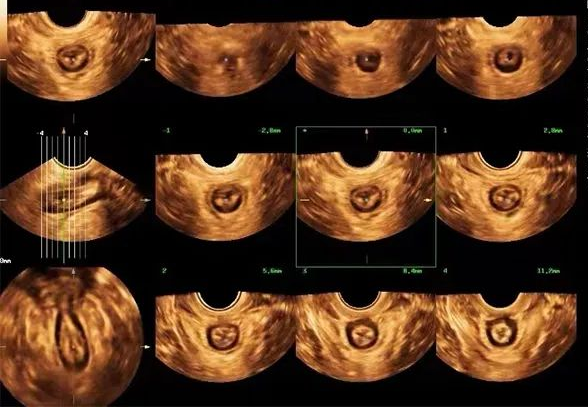

自贡市第一人民医院超声医学科主任吴萍介绍到,对于盆底功能障碍性疾病,最常见的一种检查方式就是盆底超声。这种检查具有无辐射、无创伤、可重复性好、实时动态、价格低廉等优势,有利于疾病的早期发现、早期诊断等优点。盆底超声通过利用超声探头经会阴、阴道或直肠检查,观察在静息、缩肛及Valsalva(乏氏动作,也就是我们常说的吸气、憋气)三种状态下的盆腔脏器位置变化,结合二维、三维、四维多种成像方法评估盆腔脏器脱垂程度、肛提肌裂孔大小及肛提肌、肛门内外括约肌的完整性,同时能评估尿道、阴道及肛门周围病变,也能用于盆底修复术前、术后及盆底康复疗效的评估。

d1.png 断层超声成像模式评估肛提肌及肛门括约肌连续性像妊娠及分娩后盆底功能评估、排尿异常,压力性尿失禁、排尿困难、排便障碍,大便失禁、便秘、阴道前壁、阴道后壁膨出、子宫脱垂、肛提肌和肛门括约肌等盆底肌损伤等患者都可以适用盆底超声进行检查。